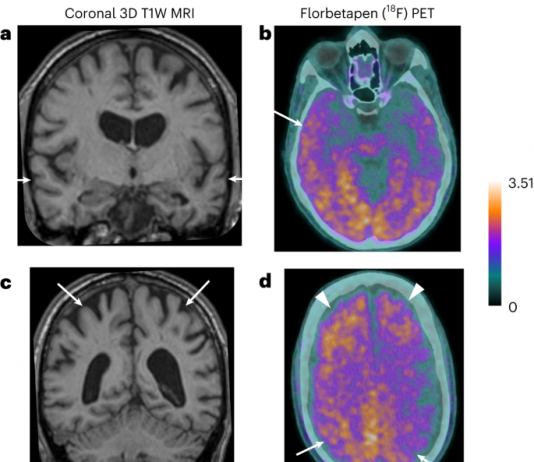

기억력과 인지능력이 저하되는 알츠하이머병은 유전자, 환경, 생활습관 등이 원인이 되어 발병하는 것으로 알려져 있다. 그런데 2024년 1월 29일(현지시각) 학술지 네이처 메디신(Nature Medicine)에 게재된 논문(Iatrogenic Alzheimer’s disease in recipients of cadaveric pituitary-derived growth hormone)에서 '시체에서 추출한 성장호르몬을 투여하는 의료 시술로 인해 알츠하이머병이 전염됐을 가능성이 있는 사례'가 새롭게 보고됐다.뇌에서 발생하는 신경퇴행성 질환인...